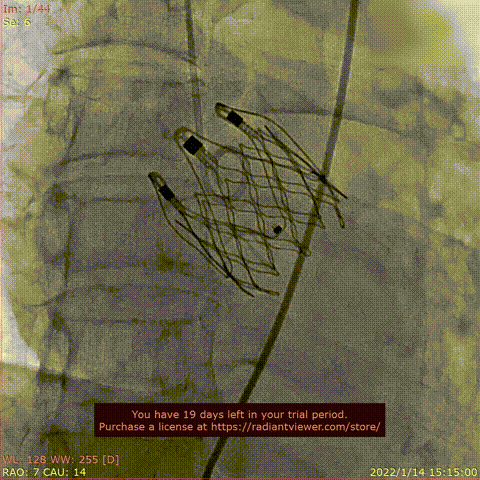

Case 4

患者为72岁男性,因“反复心累气紧10月余,加重半年 “主诉入院。术前超声提示左室肥大,双房增大,主动脉增宽,LVEF 37%,主动脉瓣重度反流。术后即刻主动脉瓣大量反流消失,平均跨瓣压差显著降低为4 mmHg,心功能显著改善。

瓣膜释放过程